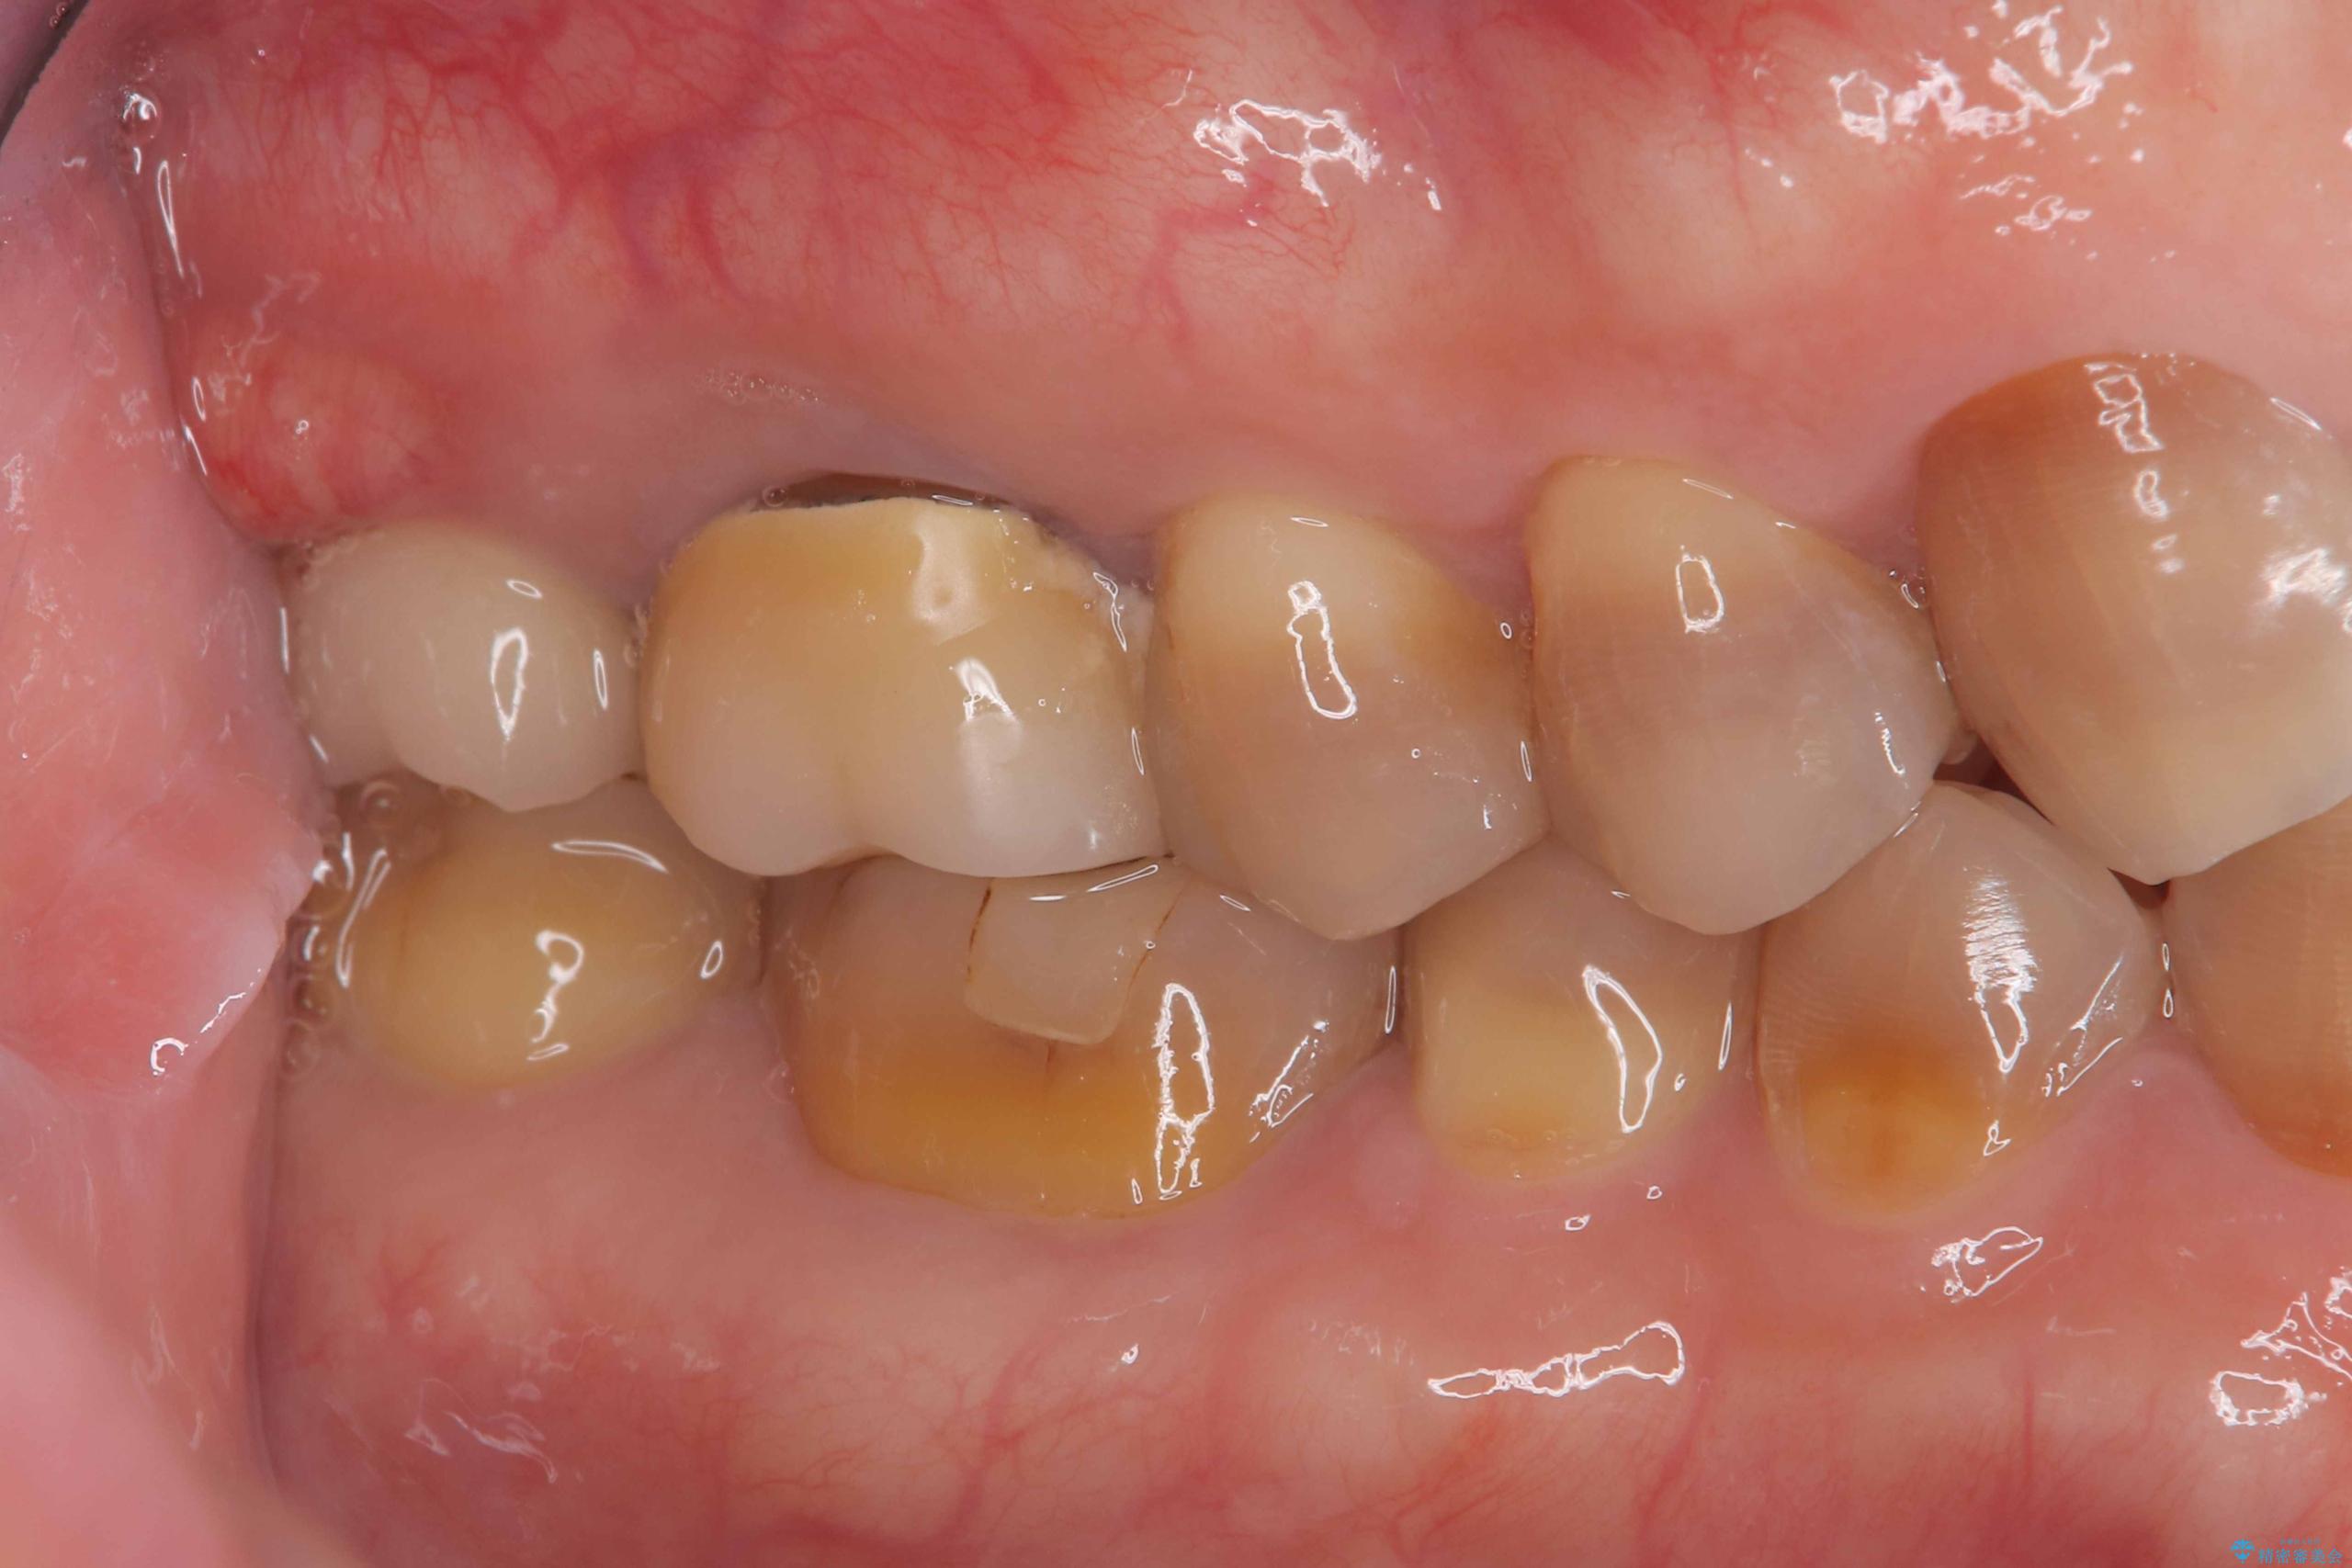

- 治療計画

- 右上7番に瘻孔を認め、根管治療を実施しましたが、瘻孔が再発し治癒が得られなかったため、抜歯のうえインプラントによる補綴治療を行いました。

抜歯と歯根嚢胞の除去を行った後、インプラントで治療しました。治療後は「自分の歯のように咬める」と大変ご満足いただけました。